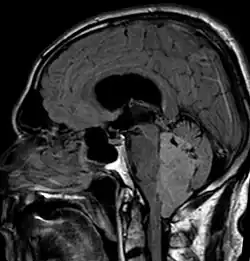

In Kernspintomografie-Aufnahmen des Kopfes stellt sich das Ependymom typischerweise als umschriebene Läsion mit Bezug zum Ventrikelsystem dar, die ein heterogenes Signalmuster mit zystischen Anteilen aufweist sowie mäßig und girlandenartig Kontrastmittel anreichert. In 50 % sind in der Schnittbildgebung Verkalkungen zu erkennen. Zytologische Untersuchung der Cerebrospinalflüssigkeit sowie Tumorbiopsie können zur Diagnosefindung beitragen.